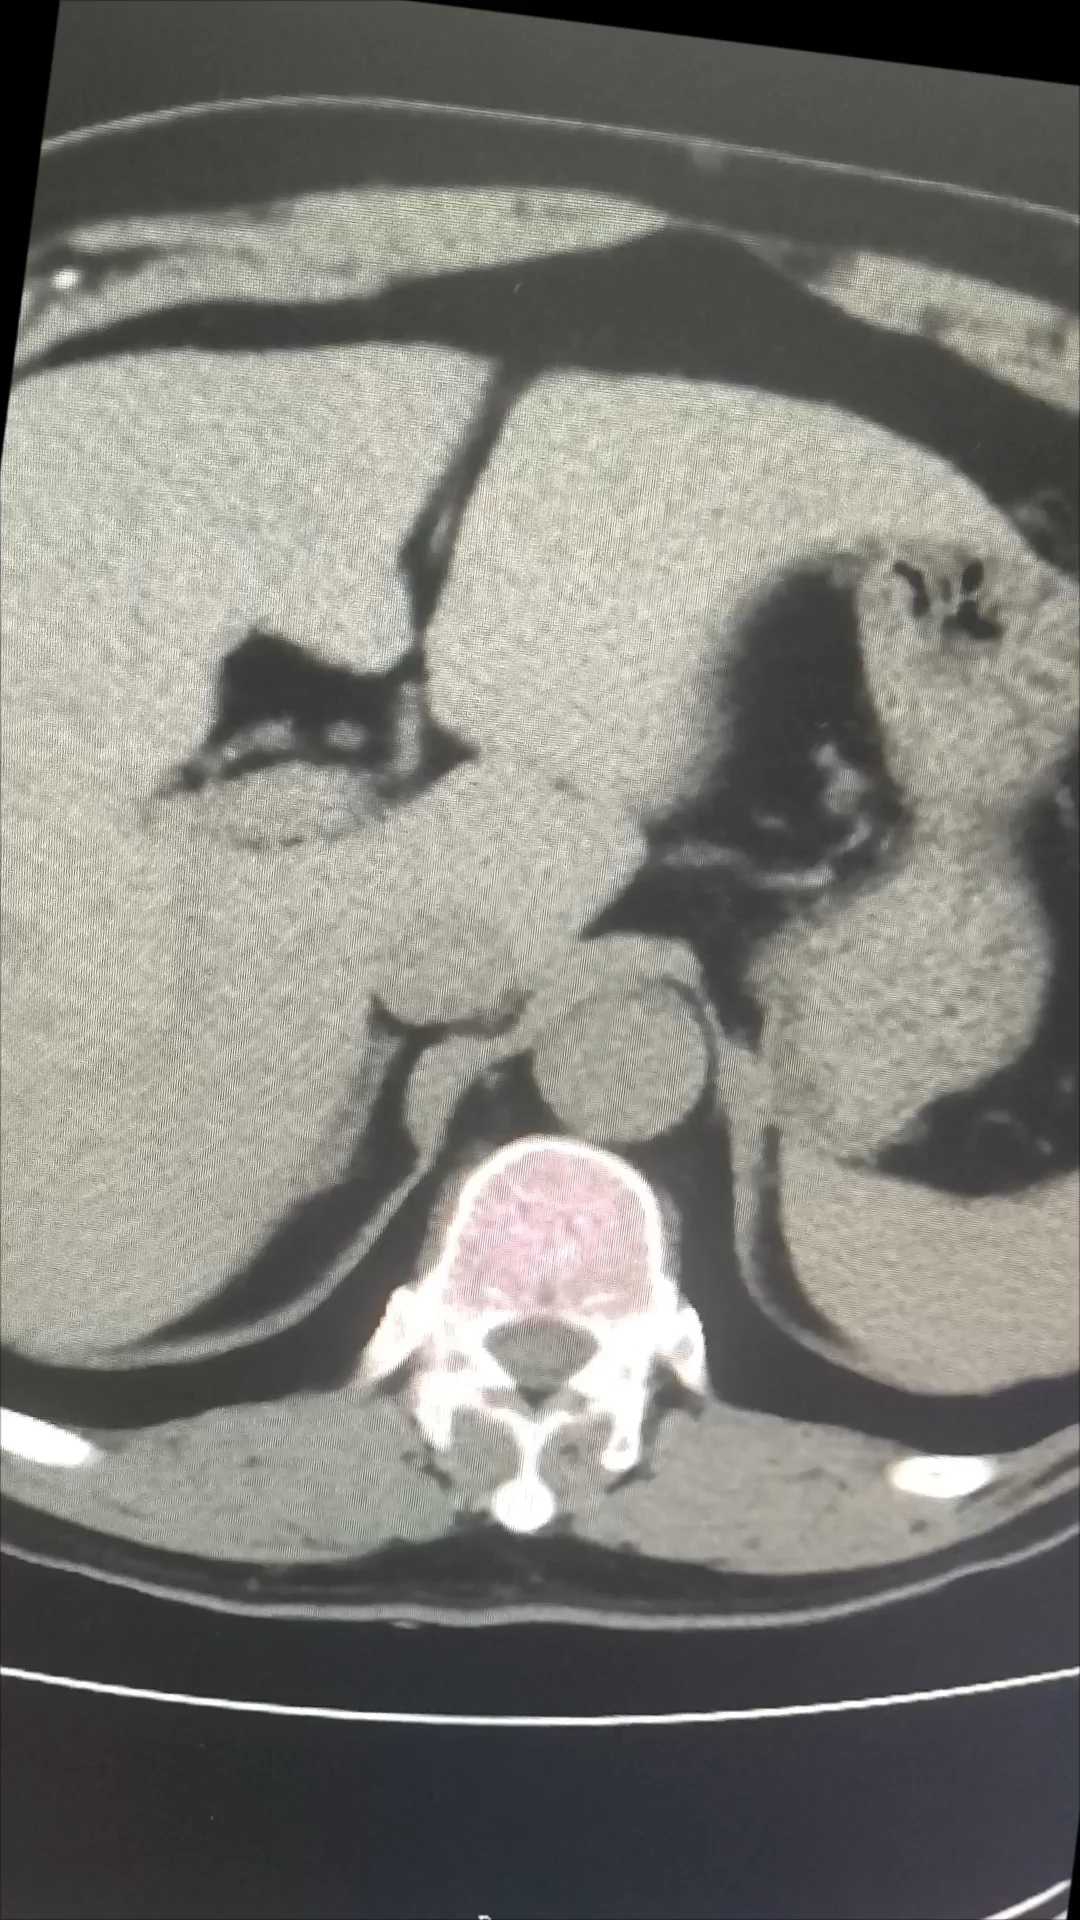

考虑若为此类疾病,我院无法完成这类疾病的治疗,本着为患者节约经济成本,未在进一步检查,让患者转入上级医院进一步明确诊断和治疗。数日后进行了回访,也证实了怀疑的真实性。手术后我院复查状况

【临床诊断】:1.肾上腺素瘤;2.低钾血症;3.高血压病2级。